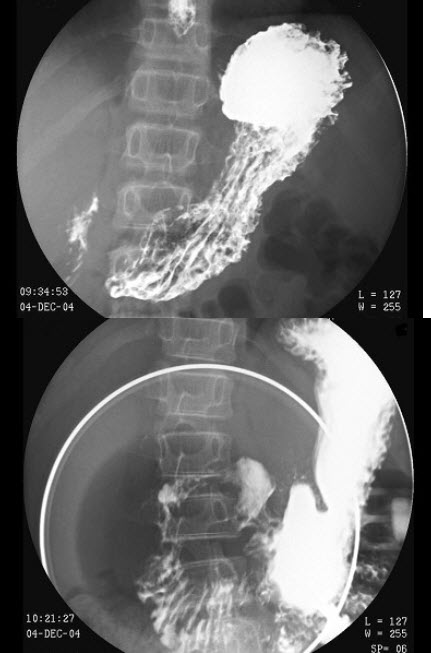

E.环形狭窄

男,12岁,上腹痛1周,无规律,无黑便史。体检:剑突下有压痛,结合图像,最可能的诊断是()

A.正常表现

B.胃炎

C.十二指肠炎

D.十二指肠溃疡

E.十二指肠占位